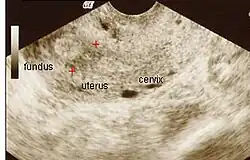

Im Ultraschall lassen sich Hinweise auf das Krankheitsbild finden. Das Endometrium lässt sich meist nur mit Schwierigkeit identifizieren. Je nach Lokalisation der Verwachsungen kann ggf. auch eine Hämatometra darstellbar sein.

Im Vergleich zur Hysteroskopie, welche heute die Standardmethode zur Diagnostik darstellt, hat die transvaginale Sonografie jedoch nur eine Sensitivität von 52 % und eine Spezifität von 11 % beim Nachweis von intrauterinen Verwachsungen.[4] In der dreidimensionalen Ultraschalluntersuchung (3D-Sonografie) zeigt sich in den betroffenen Bereichen ein vermindertes Endometriumvolumen.[7]